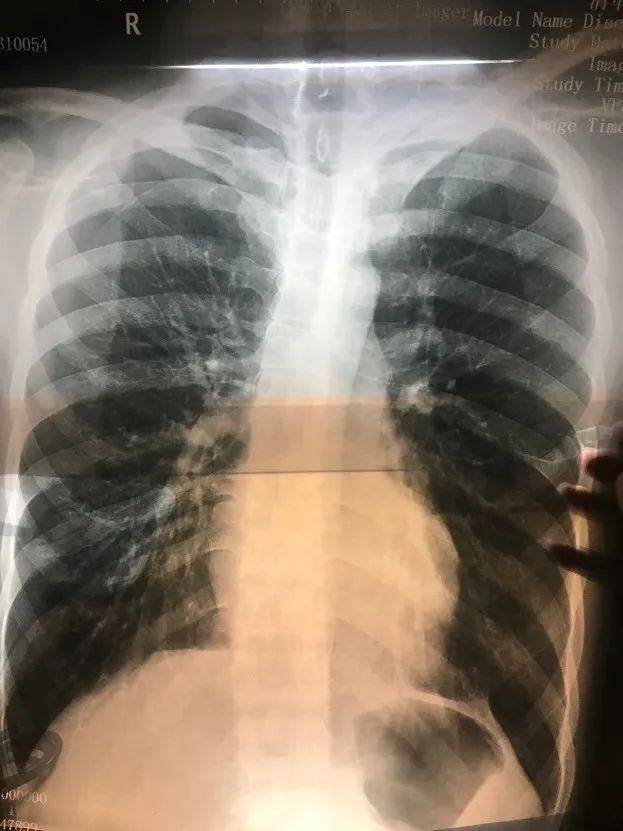

当时小山的胸片

图片来自受访者

医生看了胸片后严厉指出,胸腔里有明显的积液,很可能是血;而如果是血,情况就相当危急,必须当晚立刻进行手术。